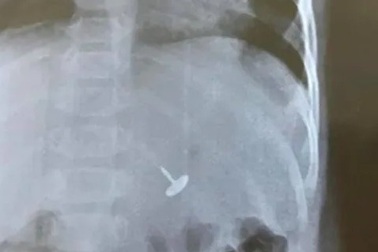

Đinh vít chui tọt vào dạ dày bé trai 11 tháng tuổiNgay sau khi phát hiện con trai 11 tháng tuổi nuốt dị vật là một chiếc đinh vít dài, gia đình vội đưa trẻ đến Trung tâm y tế huyện Tiên Yên, tỉnh Quảng Ninh khám cấp cứu.